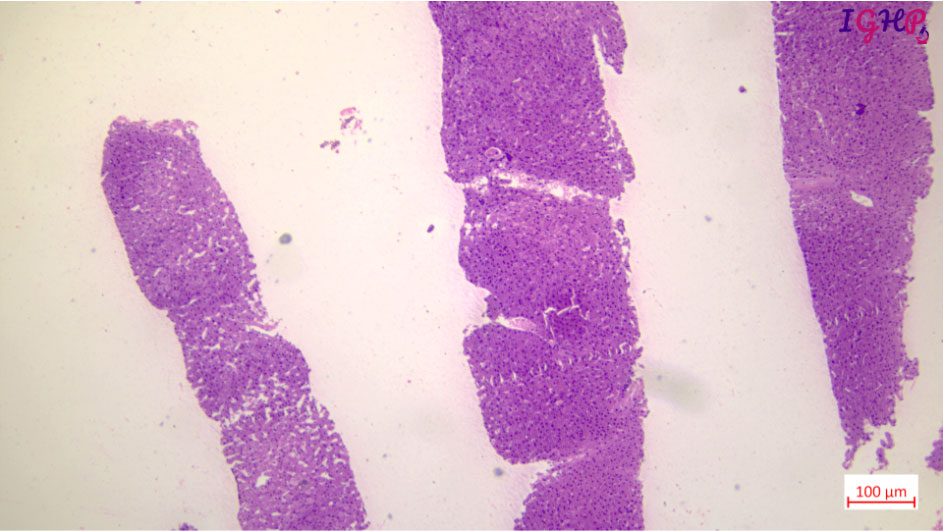

Microscopic Images-

Microscopic examination showed variable distortion of liver architecture with irregular distribution of portal tracts. At places the tracts appear atrophic with areas of close approximation. Few tracts showed absence of portal venous profiles and hypertrophied arterial vessels. There is presence of thin delicate blind ended fibrous septae around few of the portal tracts.